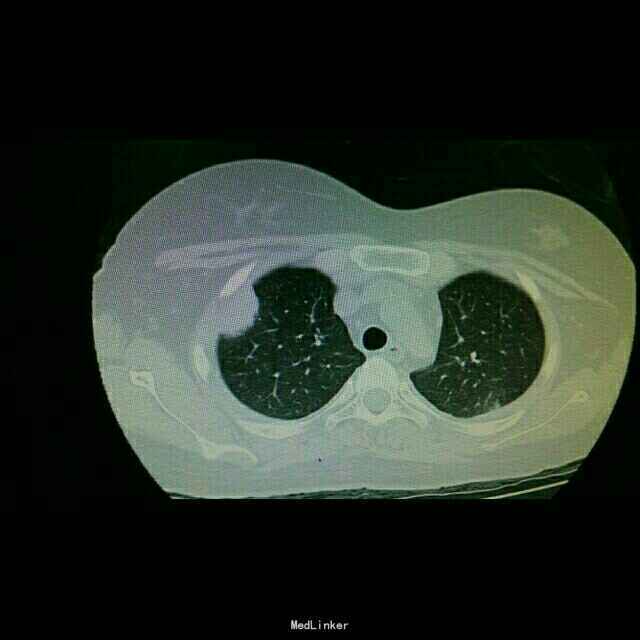

主诉:发热15天 病史:患者因视神经脊髓炎在我院神经内科住院,予以激素治疗。后因发热转我科。

查体:双肺湿罗音,余无特殊。 辅查:9.10胸部CT双肺炎症。10.2原炎症部位出现空洞。10,21原炎症部位好转,空洞无明显变化。

诊断:肺曲霉病。 治疗:开始予以伏立康唑治疗,仍有发热,后予以两性霉素*B治疗。